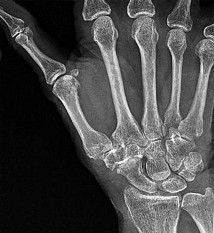

- الأشعة السينية (X-rays): هي الخطوة الأولى في تقييم الكسور، الخلوع، وتغيرات التهاب المفاصل. تساعد في تحديد مدى تدهور العظام والمسافات المفصلية. على سبيل المثال، تُظهر صور الأشعة السينية كسور السلاميات

أو كسور قاعدة العظم المشطي الخامس

، بالإضافة إلى علامات مثل "الدمعة الشعاعية" (Radiographic Teardrop) في الرسغ التي تمثل الزاوية الزندية الراحية الحرجة للكعبرة البعيدة